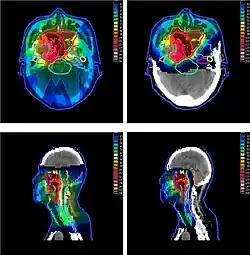

_and_IMRT_(left).jpg)

Рандомизованные исследования эффективности протонной терапии продолжаются до сих пор для разных видов рака[30] и показывают снижение частоты и последствий побочных эффектов сравнительно с другими видами лучевой терапии. Авторы из Стэнфордского университета опубликовали в 2020 году результаты исследования, выполненного на свыше чем 450 тысячах пациентов, из которых 5867 получили лечение протонным пучком[31]. Исследование показало трёхкратное снижение риска появления вторичных новообразований по всем видам рака, и 5-кратное для рака предстательной железы.

Главным преимуществом протонной терапии перед фотонной радиотерапией с модуляцией интенсивности (IMRT) является снижение побочных доз, получаемых здоровыми тканями, в особенности позади пика Брэгга. Таким образом, протонная терапия применяется чаще всего в случаях, когда опухоль расположена в тесном окружении жизнено важных органов (organs at risk — OAR): опухоли мозга, шеи, основания черепа. Также, предпочтение протонам часто отдаётся в случае лечения заболеваний у детей[32], поскольку большая ожидаемая продолжительность жизни и активно делящиеся клетки растущего организма требуют снижения побочных доз облучения[33].